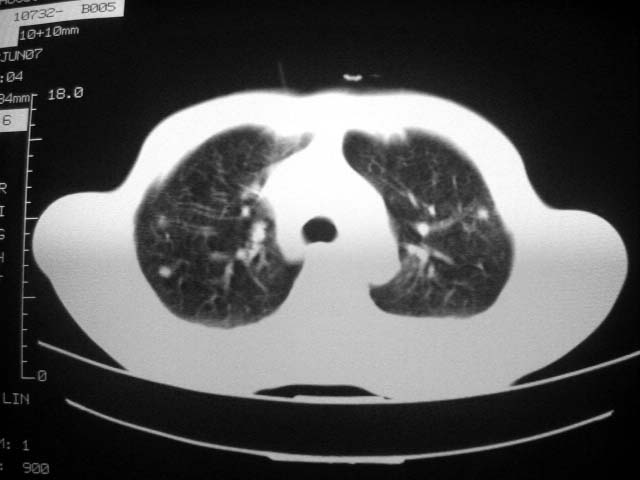

标题: CT7988D:近期图像 出乎意料!

从ct7988c 至今未用任何抗生素及抗痨药,维持保肝治疗。患者低热、咳血渐消失。

07年6月22号复查

前几次大家认为是转移癌,但此次复查病灶却明显吸收好转,不支持诊断。请大家讨论。[emb10]